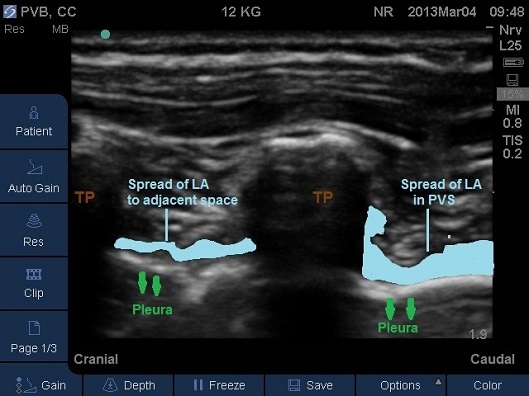

- Correct placement of the needle in the thoracic Paravertebral space should be confirmed by the anterior displacement of pleural upon injection of a small bolus of saline or local anaesthetic (Fig 13-16).

- Once confirmed the required volume of local anaesthetic should be injected.

Fig 16. Paravertebral space filled by local anaesthetic. TP –transverse process.